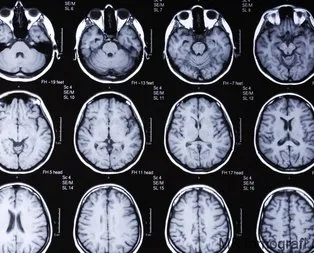

Çiğ et yedi tüm beynini tenyalar sardı

Çin'de bilinç kaybı nedeniyle hastaneye kaldırılan bir adamın, beyninde ve göğsünde yüzlerce tenya olduğu ortaya çıktı. Pişmemiş çiğ domuz eti yediği öğrenilen adamın doltoru yaptığı açıklamada, "Hastalar...